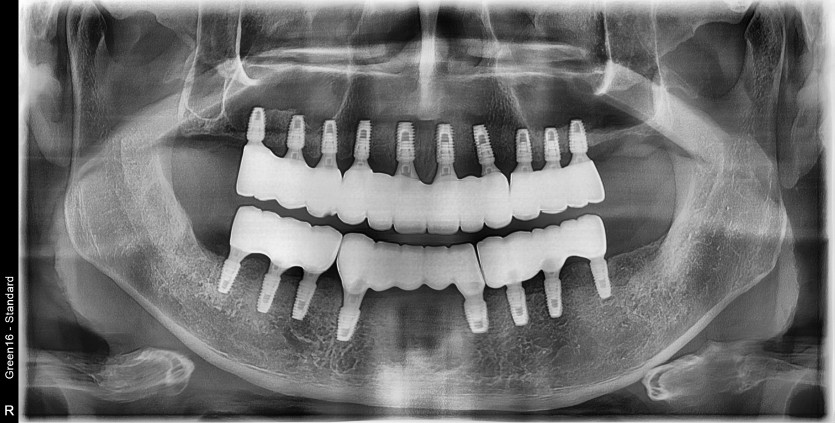

전체 임플란트 증례입니다.

18개의 임플란트로 완성하였습니다.